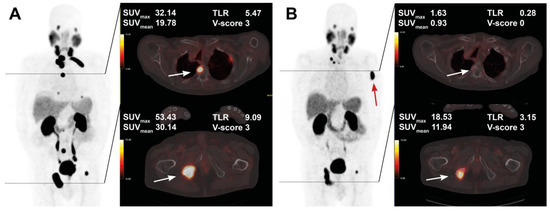

The course of all lesions per patient is depicted in Figure 3. In 11 patients showing lesion response in included baseline tumor sites, ≥2 new onset lesions on posttherapeutic imaging led to discontinuation of RLT. Examples of intraindividual lesion response on [68Ga]Ga-PSMA-11 PET/CT imaging are provided in Figure 4 and Figure 5.

Figure 5. Pre- and post-treatment images in an 83-year-old patient after 5 cycles of RLT with cumulative 35.1 GBq [177Lu]Lu-PSMA-617. Maximum intensity projection (MIP) images (left) with cross-section fusion images in a thoracic and pelvic plane at baseline (A) and after RLT (B). Lesions (white arrows) with intense baseline uptake showing response to RLT; a new bone metastasis develops in the left humerus (red arrow).